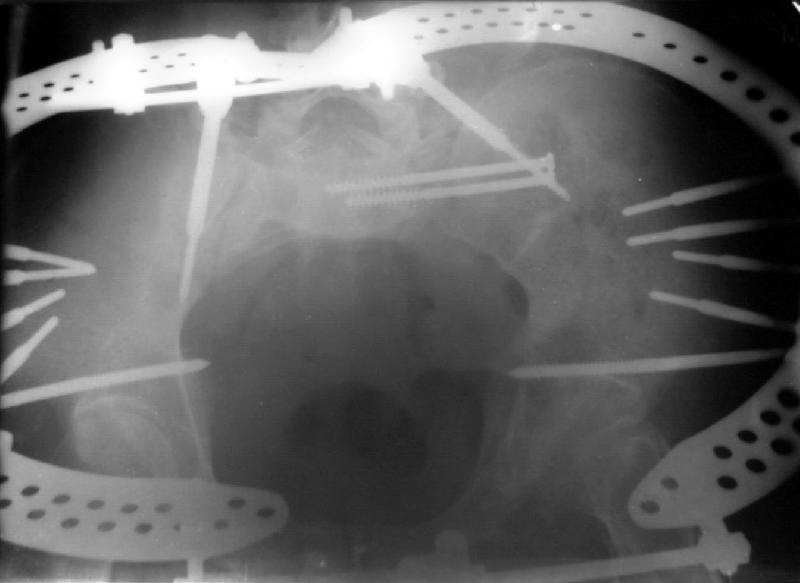

I did as suggested, I performed a 2-stage procedure (posterior sacral osteotomy and anterior take-down of left-sided rami fractures and anterior plate and percutaneous iliosacral screw fixation). It was a difficult and humbling experience. I felt as though the sacral osteotomy was complete and seemed so using intraoperative image views (inlet, outlet and true lateral of the sacrum) however after placing the distractor anteriorly I found that I could not see the sacrum well due to the bulk of the distractor itself. I then replaced it with radiolucent external fixation bars and noted widening of the left anterior SI joint.

Apparently my sacral osteotomy was not complete and the rotational correction (lateral and inferior) was occurring through the SI joint, at least anteriorly. An intraoperative x-ray showed definite improvement of the leg length discrepancy but not complete. I felt that in addition to the rotational correction the left hemipelvis also needed to move inferior as well. Due to the patient's small size, traction on her left leg simply produced pelvic obliquity and I really did not have a way of placing well leg traction which would require a post and at the same time obtain adequate intraoperative image views. Long and the short is I accepted a less than perfect reduction but with leg lengths now with less than 1 cm difference clinically and radiographically and I fused her left SI joint. No post-op nerve deficits. It was definitely a learning experience.

Any and all feed back is appreciated. Postop pics enclosed.

Intraoperative fluoro can be misleading regarding deformity corrections...maybe consider plain films when needed. Notice this lady's external rotation of the left hemipelvis postop and its impact on the acetabular coverage...see the inlet(caudal) view with attention to the ischial spine assymetry.